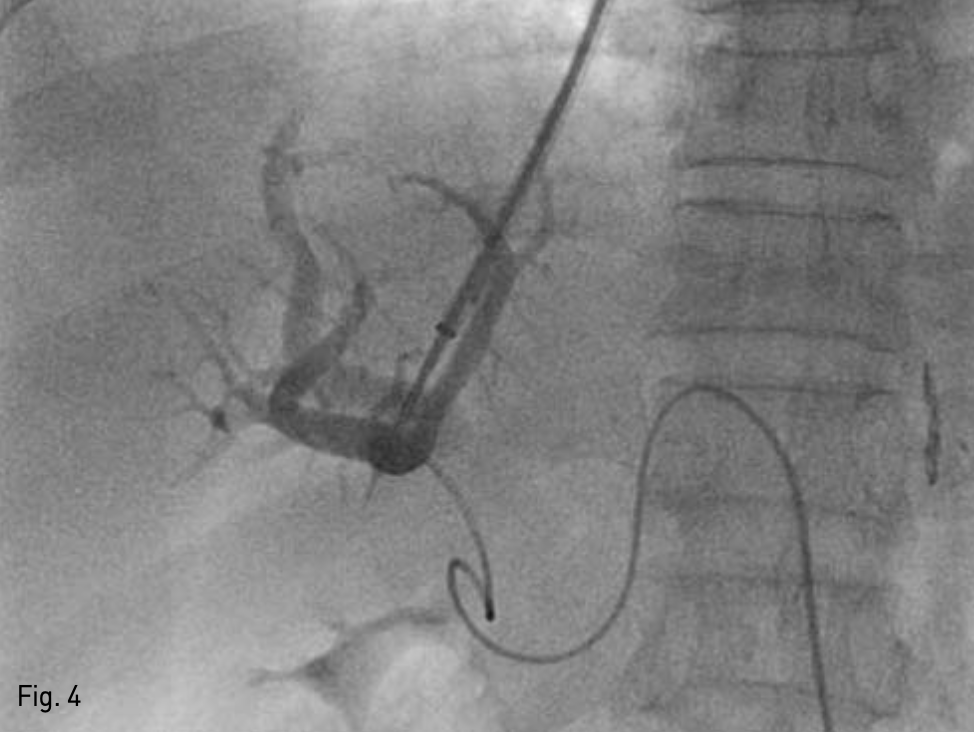

복벽에 확장되어 있는 recanalized paraumbilical vein을 초음파 유도하에 천자하여(Fig. 3), 왼쪽 문맥 으로 5-Fr 카테터를 삽입하였다. 문맥조영술을 시행하여 간내문맥을 확인하였다. Right intrnal jugular vein을 천자하여 5-Fr 카테터를 삽입하여 오른쪽 간정맥 조영술을 시행하고 오른쪽 간정맥을 신택한다. 이후 recanalized paraumbilical vein을 통한 문맥조영술 을 roadmap으로 이용하여 16G Colapinto needle (Cook Inc, Bloominglon, IN, USA) 오른쪽 간문맥을 천자하였다(Fig. 4). 천자된 경로를 6mm x 4cm balloon (Mustang, Boston Scientific, Massachusetts, USA)을 이용하여 확장하고, 10mm x 5cm partially covered stent (Niti-s TIPS Stent, Tae Woong medical, Gyeonggi-do, Korea)를 간문맥과 중간간정맥 샛길에 삽입하였다. 이후 스테트가 펴지지 않은 부분을 펴기위해 10mm x 4cm balloon (Mustang, Boston Scientific, Massachusetts, USA)을 이용해 확장하였다. TIPS stent를 설치한 후 시행한 문맥조영술에서 식도정맥류를 보이지 않았고 stent를 통한 원활한 혈류를 확인 할 수 있었다(Fig. 5). 문맥의 평균압력이 시술 전 22mmHg에서 시술 후 14mmHg로 감소하였고, 최대 정맥문맥 압력차이가 16mmHg에서 1mmHg로 감소하였다.

Fig. 4

Right portal vein puncture assisted by paraumbilical vein. Successful puncture of portal vein was done with portogram assisted by recanalized paraumbilical vein.